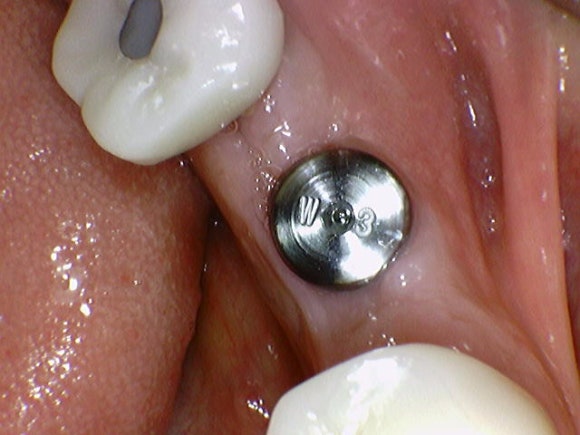

20250210

임플란트 뿌리를 노출시켜

크라운(머리부분)을 만들 준비를 합니다.